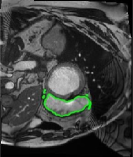

4.4 Comparison with cardic MR images for left ventricle segmentation

In this section, we continue to conduct experiments on cardiac MR images. However, we focus on the right ventricle, which is equally important as the left ventricle in cardiac MR diagnoses. In the near short-axis view, the left ventricle has a crescent shape, while the right ventricle is closer to circular. This does not imply that the right ventricle is easier to segment; in the MR images we use, the right ventricle often shows low-signal-intensity shadows, which may be caused by the imaging characteristics of certain tissues or fluids, leading to interference in segmentation. Moreover, there is a layer of myocardial tissue surrounding the right ventricle that overlaps with the boundary of the right ventricle, posing challenges for accurate identification.

Fig. 8 presents the segmentation results of the right ventricle from the DRLSE-ADMM [WALI2023109105], ABC model [WENG2021115633], RESLS [8765635], the RefLSM, and the ground truth. The results from the DRLSE-ADMM model in the 1st row reveal severe local minima due to low-signal-intensity shadows in the right ventricle. Additionally, both the ABC and RESLS models fail to correctly identify the right ventricle boundary because of the interference from surrounding myocardial tissue, as seen in the 1st and 3rd columns of Fig.8. In comparison, the proposed model gets more satisfactory segmentation results that are closer to the ground truth. Similarly, we evaluate the segmentation performance of all models by calculating the Dice and Precision values and drawing Fig. 9. This overlay plot presents the best, median and worst segmentation results, along with the overall range of outcomes that it is clear that the proposed model segments the right ventricle with greater accuracy than the other models and performs well in different images.